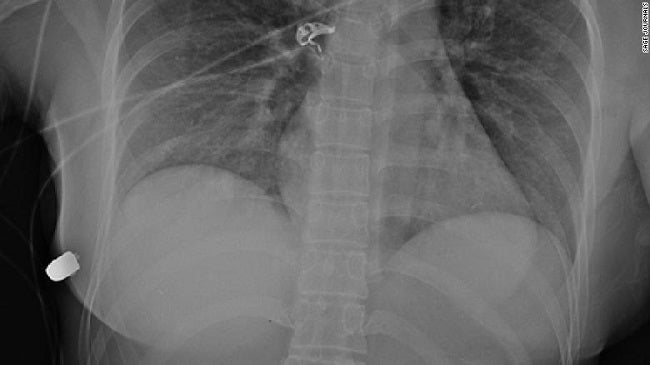

اكتشف الأطباء في أحد المستشفيات الكندية أن امرأة نجت من طلقة نارية قريبة من قلبها بفضل حشوة "سيليكون" كانت قد زرعتها في ثديها سابقًا.

وكشفت دراسة نُشرت في مجلة SAGE الطبية الأسبوع الماضي، وصف فيها الأطباء أن حشوة "السيليكون" حرفت وغيرت مسار الرصاصة وأبعدتها عن أعضاء المرأة الحيوية.

وبعد إدخالها لغرفة العمليات، اكتشف الجراحون جرحًا واحدًا وأزالوا رصاصة من تحت صدرها الأيمن، ثم أزالوا حشوة السيليكون وصوروها بهدف دراستها وقد أظهرت الأشعة المقطعية أن الرصاصة مرت عبر الحشوة اليسرى وضربت اليمنى.

وقال الجراح: "بناء على مسار دخول الرصاصة وتقويمها إشعاعيًا، فإن المصدر الوحيد لانحراف الرصاصة هو حشوة الثدي الأيسر".

وأوضح: "على الجانب الأيسر يوجد القلب والرئتان، لو أن الرصاصة دخلت في الصدر لتعرضت الشابة لإصابة أكثر خطورة".